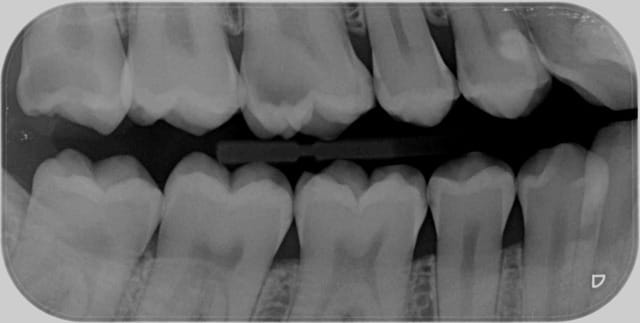

De plus, quand on utilise le QS, ce serait une erreur de le garder seulement pour les molaires mandibulaires. Voir la radio bite-wing de mon patient de ce matin pour le secteur 1: 1 carpule entre 16-17 et 1/2 entre 14-15 et j'ai pu soigner de 14 à 18. Aucune douleur lors de la réalisation de l'anesthésie, pas besoin "d'attendre que ça prenne", pas d'engourdissement de la joue, et anesthésie complète des dents + des tissus mous, ce qui est drôlement pratique pour passer les coins interdentaires lors de la pose des matrices.